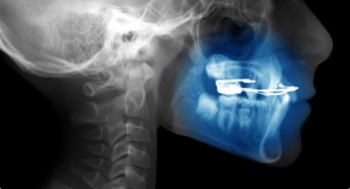

Oferujemy wysokiej jakości badania diagnostyczne, takie jak: RTG punktowe, pantomogram, cefalometria, tomografia CBCT, cyfrowy skan zębów oraz dentystyczny protokół fotograficzny.

Efektywne leczenie stomatologiczne w większości przypadków wymaga dokładnej diagnostyki, opierającej się na zobrazowaniu stanu uzębienia, kości szczęki czy żuchwy. Jednym z popularnych sposobów diagnostyki stomatologicznej jest zdjęcie pantomograficzne, czyli pantomogram. Pozwala ono uzyskać precyzyjny obraz struktur, z odwzorowaniem wszelkich krzywizn i ewentualnych nieprawidłowości. Zaawansowaną diagnostykę zapewnia tomografia komputerowa CBCT, która oferuje obrazowanie w technologii 3D.